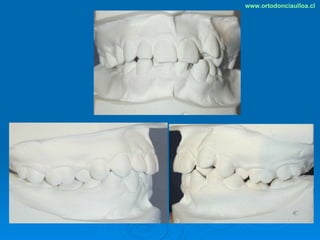

Este documento presenta dos casos clínicos de pacientes que recibieron tratamiento de ortodoncia. El primer caso fue de una paciente femenina de 14 años con apiñamiento dental y mordida cruzada que fue tratada mediante extracción de premolares y alineamiento dental. El segundo caso fue de un paciente masculino de 14 años con clase II esqueletal y desarmonía dentomaxilar que fue tratado con extracción de premolares y corrección de mordida. Ambos casos mostraron mejoría después de 3 años de tratamiento.